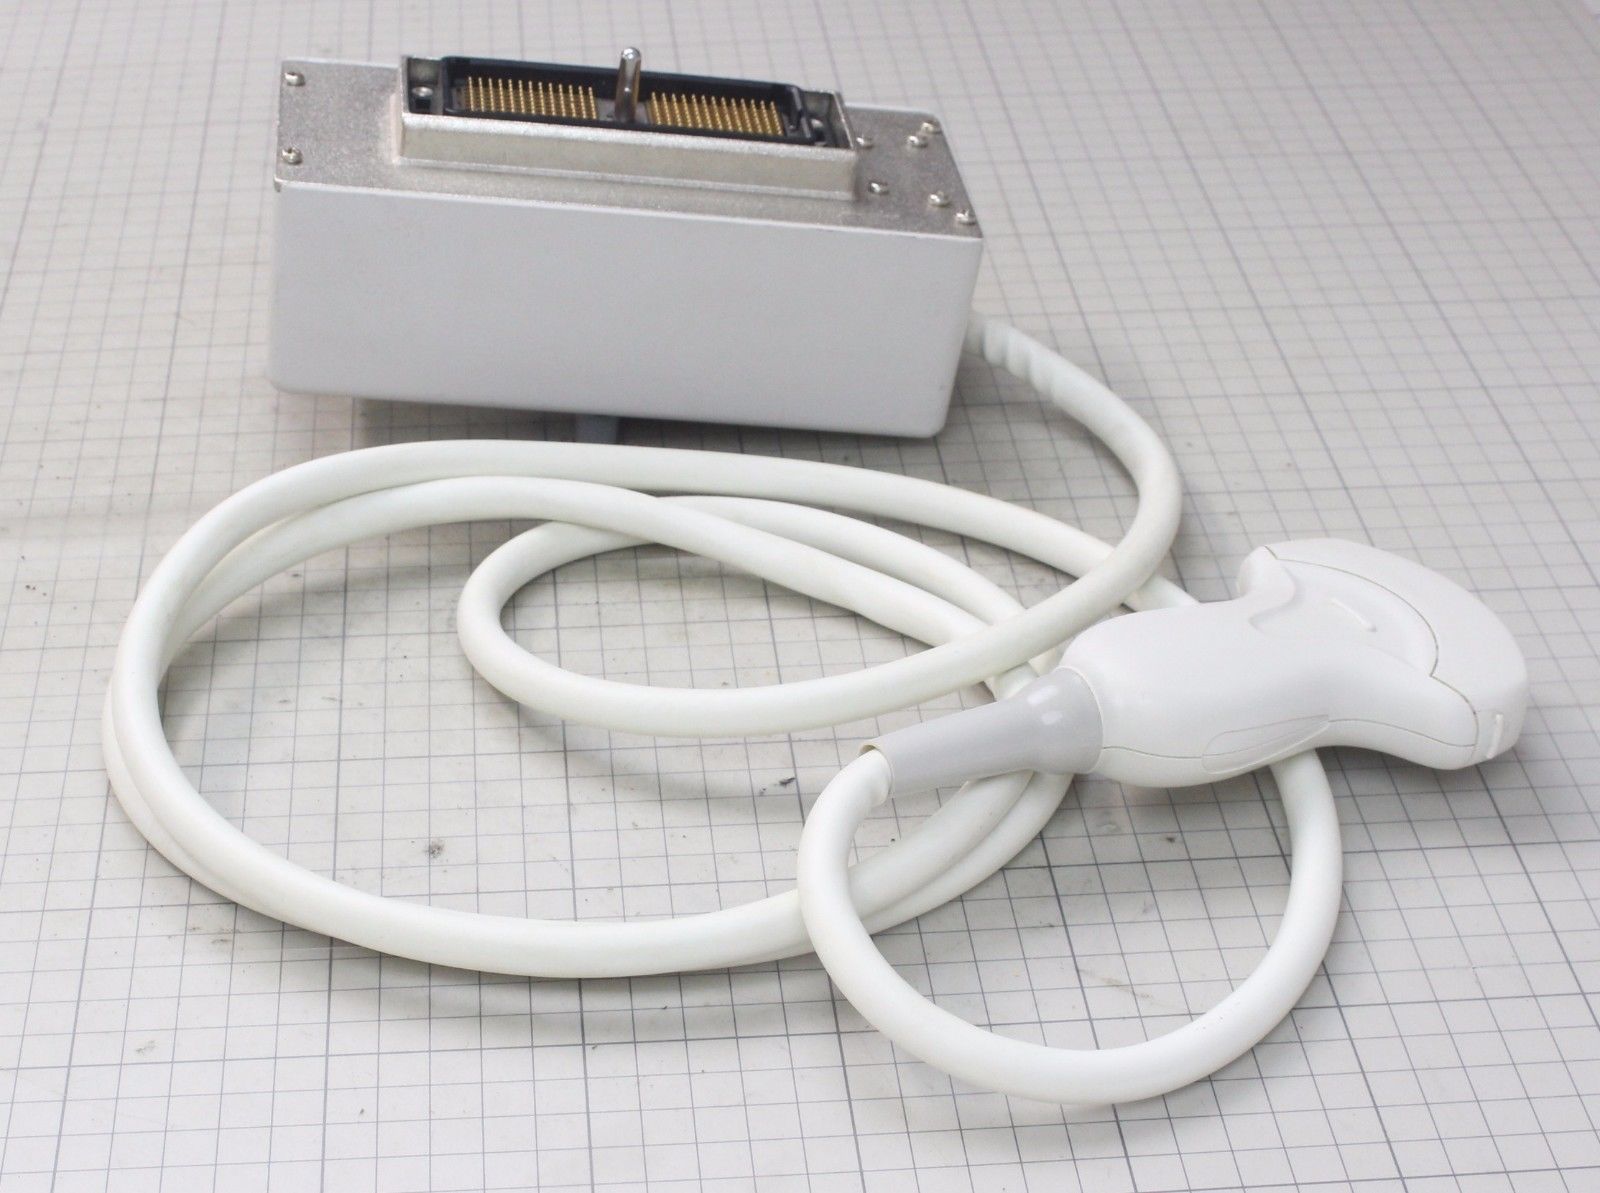

DIAGNOSTIC ULTRASOUND MACHINES FOR SALE

Samsung Medison Accuvix XG with 3D/4D convex probe

Sale price$ 47,965.06